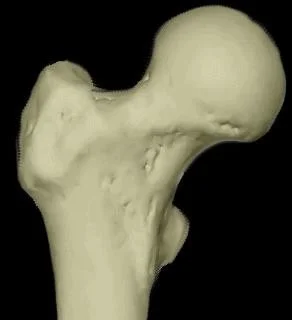

Proximal Femur Fractures

Classification

- Femoral Neck

- Intra-capsular

- Inter-trochantric

- Extra-capsular

Intra-capsular vs. Extra-capsular

- The capsule envelopes the femoral head and neck

- Intertrochanteric and sub-trochanteric fractures are extra-capsular

Femoral Neck Fractures

Vascular Supply C ?

- Anterior View

- The Lateral Femoral Circumflex Artery is shown supplying the femoral head.

- Posterior View

- The Medial Femoral Circumflex Artery is depicted as the primary supplier to the femoral head.

Risk of Avascular Necrosis

- Risk of osteonecrosis (Avascular Necrosis)

- More in near head (Sub-capital)

- More in displaced fractures